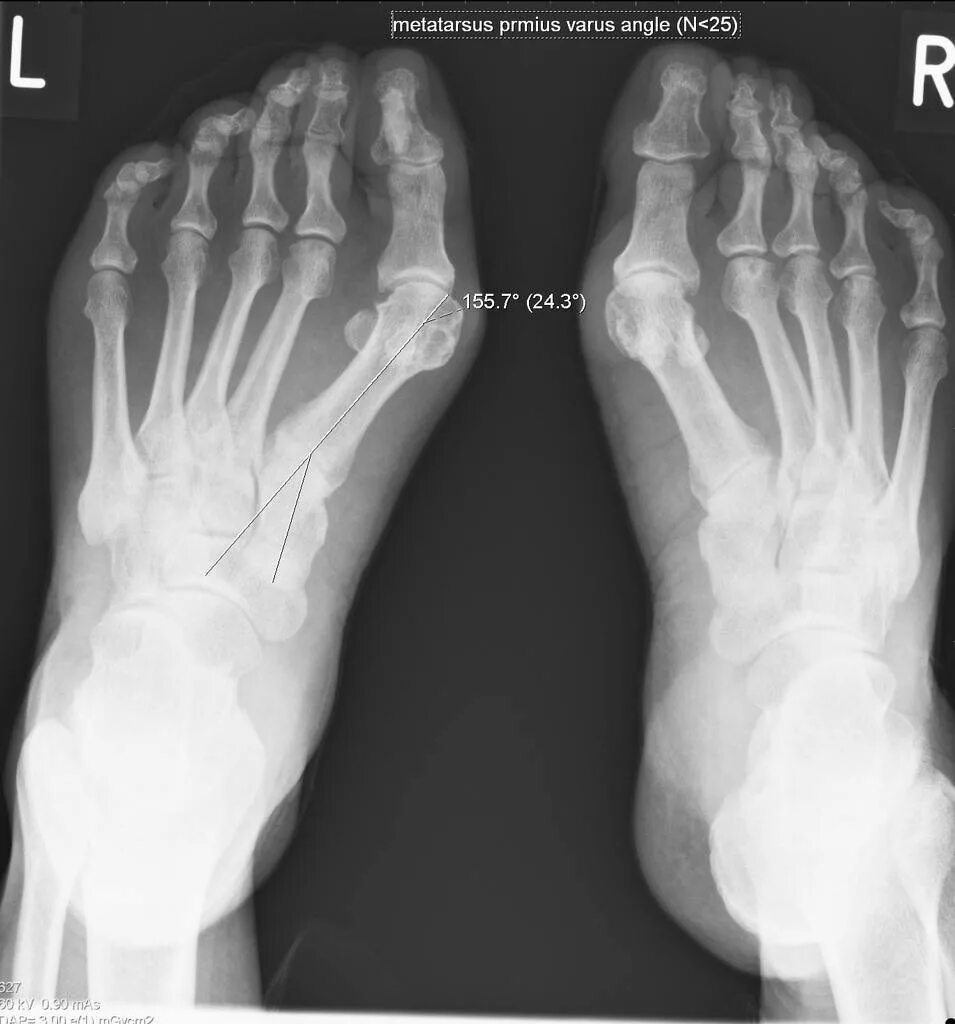

Вальгусная деформация стопы степени